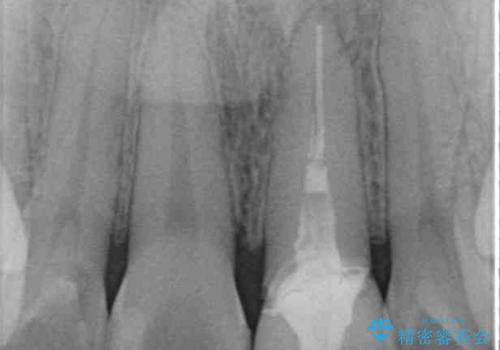

- 前歯のクラウン付近の歯肉が黒く見えることを気にして来院された患者様です。

根管治療を行った後に、オールセラミッククラウンにて補綴することとしました。